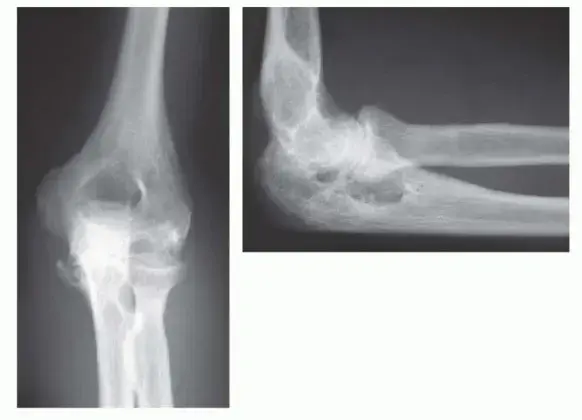

بينما قد يبدأ التهاب المفاصل الروماتويدي في مفاصل أصغر مثل مفاصل اليد والقدم، فإنه غالبًا ما ينتشر ليؤثر على المفاصل الكبيرة. يصاب مفصل الكوع في حوالي 20% إلى 70% من مرضى الروماتويد، وتتراوح شدة الإصابة من خفيفة إلى شديدة جدًا. ليس من المستغرب أن 90% من هؤلاء المرضى يعانون أيضًا من إصابة في اليد والمعصم، و80% منهم يعانون من إصابة في الكتف أيضًا. هذا يوضح الطبيعة الشاملة للمرض وكيف يمكن أن يؤثر على سلسلة كاملة من المفاصل المسؤولة عن حركة الذراع.

عندما يصاب مفصل الكوع بالروماتويد، تبدأ بطانة المفصل (الغشاء الزليلي) بالالتهاب والتورم. يؤدي هذا الالتهاب المزمن إلى تآكل الغضاريف التي تغطي أطراف العظام، وإتلاف الأربطة التي تثبت المفصل، ومع مرور الوقت، يمكن أن يتسبب في تدمير العظام نفسها. النتيجة النهائية هي ألم شديد، تيبس، محدودية في نطاق الحركة، وفي الحالات المتقدمة، تشوهات واضحة في المفصل، مما يجعل أبسط الحركات اليومية مهمة شبه مستحيلة.

• التشوهات: في المراحل المتقدمة، يمكن أن يؤدي تدمير العظام والغضاريف والأربطة إلى تشوهات مرئية في مفصل الكوع، مثل انحراف المفصل عن مساره الطبيعي.

* تلف شديد في المفصل: يظهر في صور الأشعة السينية، حيث يكون الغضروف قد تآكل بشكل كبير والعظام قد تضررت.